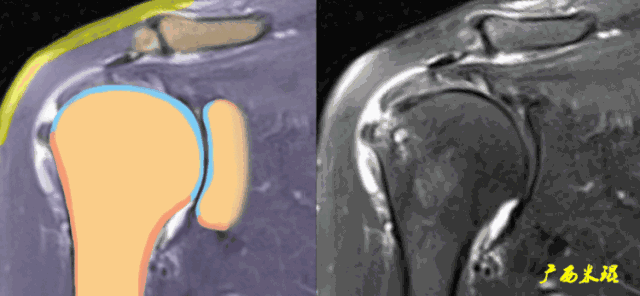

1、斜冠状位:平行于冈上肌腱长轴,主要评估冈上肌。

d、肩峰骨刺,发生肩袖撕裂的机会比钩状肩峰还要大,必须认真阅看,肩峰骨刺在斜矢状位上显示得非常清楚。

肩峰骨刺在斜冠状位上能够看到,应该认真观察并且留意其对应的肩袖面。

g、肱骨大结节的部分缺损是长时间严重撞击的表现,在斜冠状位发现缺损的同时,一般都能看到肩袖的中断和回缩。